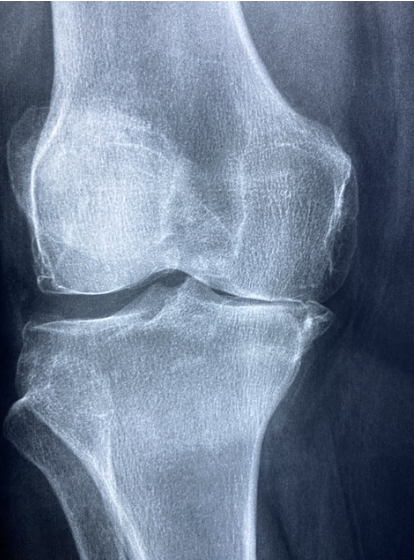

콘드로이친은 관절 연골을 구성하는 중요한 성분으로, 관절의 수분 유지와 탄력성을 증가시키는 역할을 합니다. 특히, 콘드로이친 1200mg은 관절 통증과 염증을 감소시키는 데 효과적이며, 장기적인 복용을 통해 관절의 기능을 향상시킬 수 있습니다. 관절염 환자에게 콘드로이친 1200mg 복용은 통증 완화뿐만 아니라 연골의 감소를 억제하고 염증을 줄이는 데 도움을 줄 수 있습니다.

콘드로이친의 효능은 여러 연구를 통해 입증되었습니다. 예를 들어, 하루 콘드로이친 1200mg을 복용하는 것이 관절 통증 감소에 효과적이라는 연구 결과가 있습니다. 콘드로이친 1200mg은 특히 관절의 염증을 완화하고, 관절 연골의 건강을 지원하는 데 중요한 역할을 합니다.